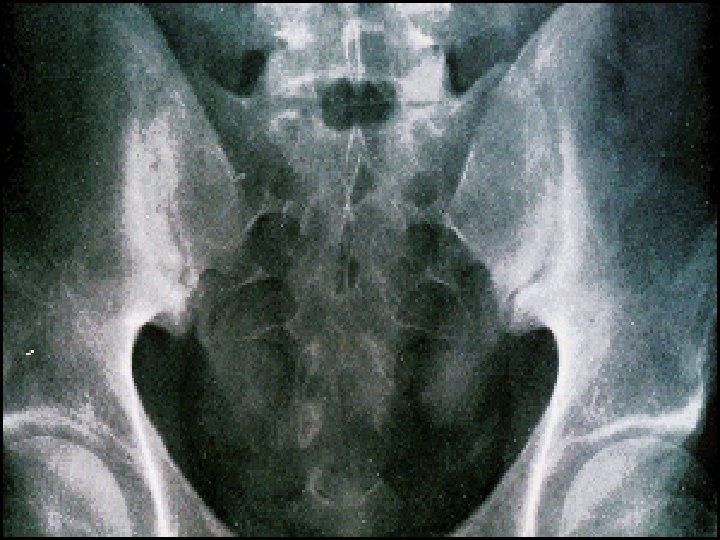

Ulcerative colitis. Double-contrast barium enema study shows pseudopolyposis of the descending colon Crohn’s disease (regional ileitis)

Imaging Ulcerative Colitis • Barium Enema vs. CT – Barium Enema is no longer the test of choice • Findings – Continuous lesions from rectum proximally with circumferential involvement n Lead Pipe Sign n n Repeated episodes of mucosal ulceration and marked muscularis hypertrophy results in shortening, narrowing and smoothing out of the normal haustral markings. “Lead pipe” appearance of colon due to chronic scarring and retraction/loss of haustra Weinstein A et al. A super ‘lead pipe’ colon: radio-pathological correlation of long-standing ulcerative colitis. SA Journal of Radiology; 2008 Oct: 70 -72

Indication for Urgent Colectomy Colonic dilatation >6 cm on plain abdominal X-Ray. Lab. & Clinical deterioration. No response after 7 -10 days.